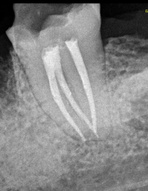

Es un procedimiento que

tiene como finalidad evitar la perdida del diente.

Para ello, se extrae la pulpa dental, se desinfecta y posteriormente se rellena y sella con material inerte y biocompatible.

¿Qué es una endodoncia?